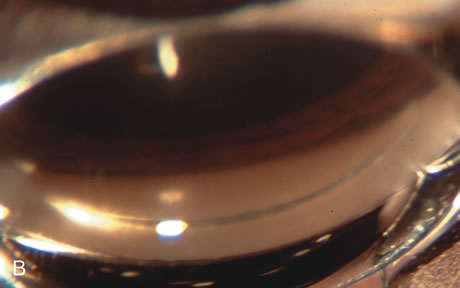

In years past, patients with both cataract and glaucoma frequently provided overwhelming surgical challenges for the ophthalmologist. The ability to carry out phacoemulsification through a 3.2-mm corneal incision along with inserting a foldable IOL is a vast improvement over 11-mm incisions that were common a decade ago (Fig. 1). The anatomical and inflammatory changes to the eye are less with small incision techniques, improving the likelihood of success with concomitant glaucoma surgery. Pharmacologic inhibition of fibrosis along with postoperative wound revision increases the long-term success rate of filtration surgery when combined with lens extraction. (Fig. 2). The learning curve may be steep at times, but the blending of cataract and glaucoma surgical skills slowly falls into place as the surgeon constantly learns and upgrades his or her technique.

Fig. 1. The anatomic advantage of small incision cataract surgery for the glaucoma patient. A. Long-term bleb function with a large cataract incision is difficult to achieve with either ECCE-trabeculectomy or trabeculectomy followed later by ECCE. This bleb failed to form sufficiently when combined with large incision ECCE. The inflammation, bleeding, and long-term wound healing with stimulation of fibroblasts associated with this technique are more likely to cause bleb failure. In addition, the increased iris manipulation necessary to deliver the nucleus and subsequent iris repair adds to the long-term breakdown of the blood aqueous barrier. B and C. Two-site phacotrabeculectomy has the advantage of small incision cataract surgery combined with separate site trabeculectomy. The incision size is one third the size of the standard ECCE. The inflammation is less severe, and cataract wound healing is confined to the temporal area. Visual rehabilitation with phacoemulsification and foldable IOL is much faster. Phacoemulsification allows successful lens extraction even in the unfriendly environment of a smaller pupil compared with ECCE. The trabeculectomy is performed in an entirely different site, well away from the wound healing associated with temporal phacoemulsification. The likelihood of this filter functioning long-term is greater than with ECCE-trabeculectomy. D. The surgeon also has the option of single-site phacotrabeculectomy with foldable IOL. Both the lens extraction and trabeculectomy are performed through one small 3.5-mm limbal incision.